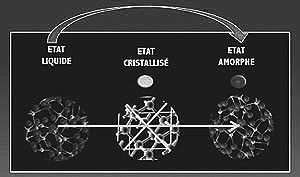

Pour toute congélation, lente ou rapide, Avant de plonger les embryons dans l’azote liquide,il faudra les préparer pour qu’ils ne soient pas confrontés à l’agression des cristaux de glace, Ce qui détruirait l’embryon et le rendrait inutilisable.

Pour celà les embryons seront déshydratés en grande partie, en remplaçant l’eau par un ou des cryo-protecteurs de type « bio-antigel ».